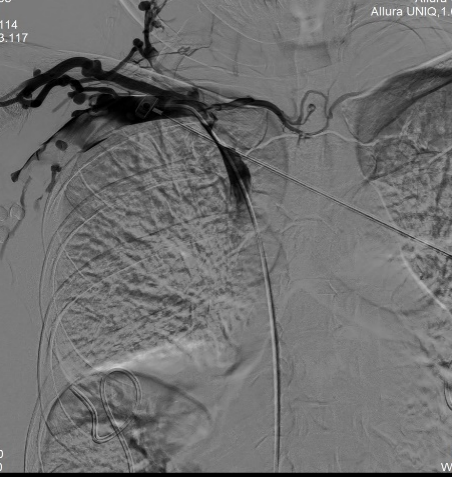

術(shù)后

DSA引導(dǎo)下精準定位釋放支架成功,再次造影,頭臂靜脈閉塞段開通,血流可順利回流至上腔靜脈,但右側(cè)鎖骨下靜脈遠心端及腋靜脈可見血栓形成,遂予以留置導(dǎo)管溶栓治療。

術(shù)后3h,患者右上肢皮膚張力明顯緩解,術(shù)后24h,右上肢腫脹明顯緩解。

術(shù)后第2日,右側(cè)鎖骨下靜脈血栓范圍明顯縮小,右上肢腫脹完全緩解。